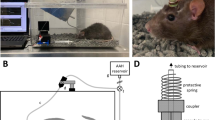

Simultaneous invasive and noninvasive IOP measurements

Simultaneous invasive and noninvasive measurements were carried out both in enucleated mouse eyes (n=12), obtained immediately after death, and in the eyes (n=8) of live animals. Half of the eyes were used for IOPG measurements; the other half was used for the determination of IOPR. Several tonometer readings were obtained from each eye while varying amounts of hydrostatic pressure were applied and the pressure was continuously monitored invasively (IOPIN) by direct cannulation. Each measurement consisted of several readings (see below) and averages of these readings are used throughout this paper.

IOP measurements in enucleated eyes and live animals were carried out in a similar manner except that enucleated eyes were mounted in a custom-built stand. Two 26-gauge steel needles were carefully inserted into the posterior segment of the eye, and care was taken to avoid contact with the lens. One needle was connected to a pressure transducer (MLTO380, ADInstruments, Colorado Springs, CO), while the other was connected to a phosphate buffer solution (PBS) infusion bottle that could be raised or lowered to establish various levels of hydrostatic pressure. Before experimentation, we ascertained that the insertion of the needles did not noticeably displace the lens and determined that the transduction of pressure through both needles was unimpeded by raising and lowering the PBS bottle several times.

Measurements were carried out in a masked manner: one investigator selected the elevation of the PBS bottle and recorded the IOP as determined by invasive manometry, while a second investigator (CYK) measured the IOP using either a rebound tonometer (Tonolab tonometer, Colonial Medical Supply, Franconia, NH) or a modified Goldmann tonometer (Haag-Streit USA Inc., Mason, OH, USA) as reported previously.4, 16

Laser-induction of ocular hypertension (OHT)

Laser photocoagulation to the limbus in the area of the trabecular meshwork was performed as reported previously.4 Briefly, mice were anesthetized with 2% isoflurane and 100% oxygen. A 3 μl portion of indocyanine green (10 mg/ml; Akorn, Buffalo Grove, IL, USA) was slowly injected into the anterior chamber of the eye using a micro-injector pump (World Precision Instruments, Sarasota, FL, USA). Twenty minutes after the injection, a diode laser (DioVet, Iridex Corporation, Mountain View, CA, USA) was used to deliver between 30–35 spots exteriorly over a 300° range of the limbus outlined by the dye (200–300 mW energy, 200–300 ms pulse duration). Following the procedure, antibiotic ointment was applied over the eye and acetaminophen (240 mg/l) and codeine (24 mg/l) were administered in the drinking water for 7 days. In each case, the left eye underwent laser surgery and the untreated right eye was used as the control.